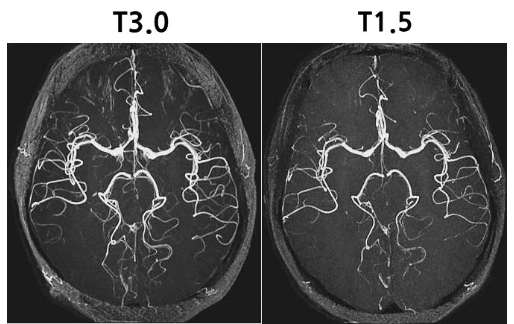

지난 포스팅에서 잠깐 언급한 적이 있지만, MRI도 자기 수준에 따라 선명도? 화질?에 차이가 있습니다. 일반적으로 1.5T와 3.0T로 나눠볼 수 있는데, 1.5T의 MRI로 찍은 영상은 3.0T와 수준 차이가 확 납니다. 제가 1.5T로 찍은 MRI 들고 갔다가 3.0T 재촬영 당한 사람이라 확실히 느껴본 바가 있습니다. 정확한 비교샷을 원하시는 분을 위해 한 병원에서 올려주신 MRI T(테슬라) 차이에 따른 비교 포스팅을 참고 링크로 남겨드립니다.

이처럼 차이가 있기 때문에, 병원에서는 정확한 진단을 위해 3.0T 짜리 MRI를 요구할 수 있습니다. 기껏 돈주고 싸다는 데서 MRI를 찍어갔는데 1.5T라 다시 찍어오라고 한다면 불상사도 그런 불상사가 없겠지요. 다른 기관에서 MRI를 찍으실 거라면 꼭! 3.0T 짜리 MRI를 가지고 있는 기관에 방문하셔서 촬영하시길 권고드립니다.